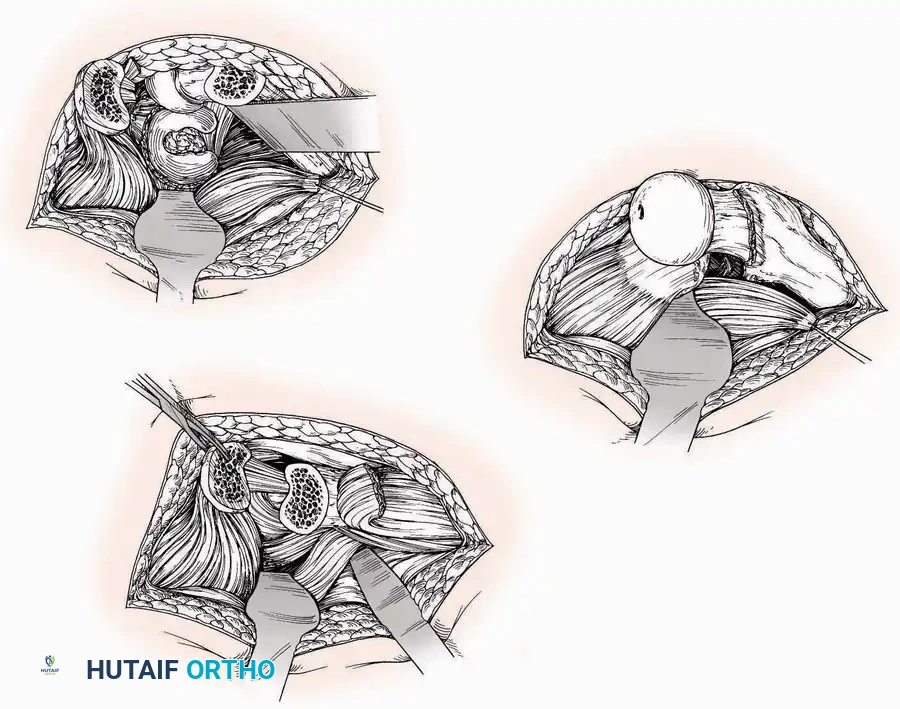

Surgical Technique:

* Incision: Begin the incision on the lateral margin of the Achilles tendon near its insertion. Extend it distally to a point 4 cm inferior and 2.5 cm anterior to the lateral malleolus. (For trauma, a classic L-shaped extensile incision is often used, dropping straight down anterior to the Achilles, then curving gently toward the base of the 5th metatarsal).

* Superficial Dissection: Divide the superficial and deep fasciae. It is imperative to create a "full-thickness" flap containing skin, subcutaneous fat, and periosteum to prevent flap necrosis.

* Nerve Protection: The sural nerve crosses the proximal and distal limbs of this approach. It must be identified and protected within the anterior flap.

* Deep Dissection: Isolate the peroneal tendons (longus and brevis). Incise and elevate the periosteum below the tendons to expose the lateral wall of the calcaneus.

* Tendon Management: If severe deformity or infection is present, the peroneal tendons may be divided via Z-plasty and repaired at the conclusion of the case, though this is rarely necessary in modern fracture care.